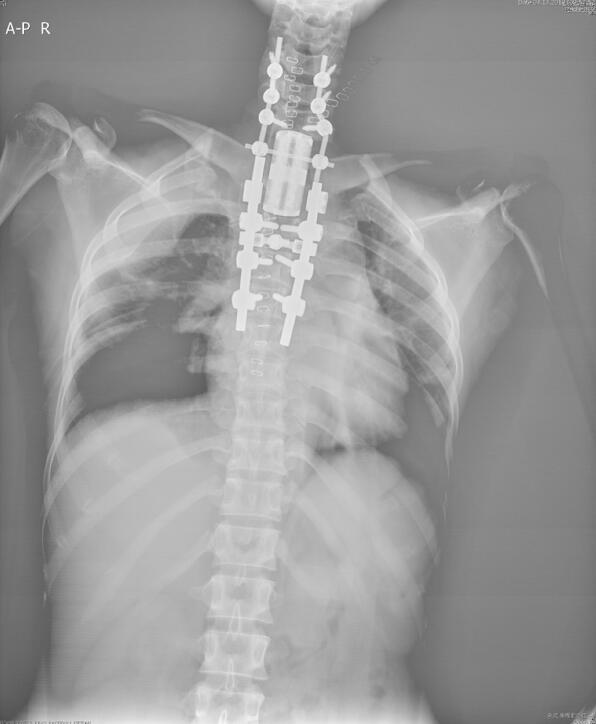

经狄诺塞麦治疗4程后,复查CT和MR见患者肿瘤明显缩小,肿瘤硬化明显。2019年2月20日,由麻醉科龙浴辉医生实施麻醉,手术室刘艳玲护长指导骨科专业队伍,患者先行仰卧位,骨与软组织科王晋教授和胸科李小东教授同台联合手术。教授们先行前路分离,接着更换为俯卧位,把第1胸椎、第2胸椎、第3胸椎一并整块切除,并使用3D打印人工椎体重建,术后骨与软组织科护理团队悉心护理,指导患者康复锻炼,患者下肢肌力逐渐改善。于术后21天,患者顺利出院,此时的下肢肌力已达到了4级。

术后复查X线